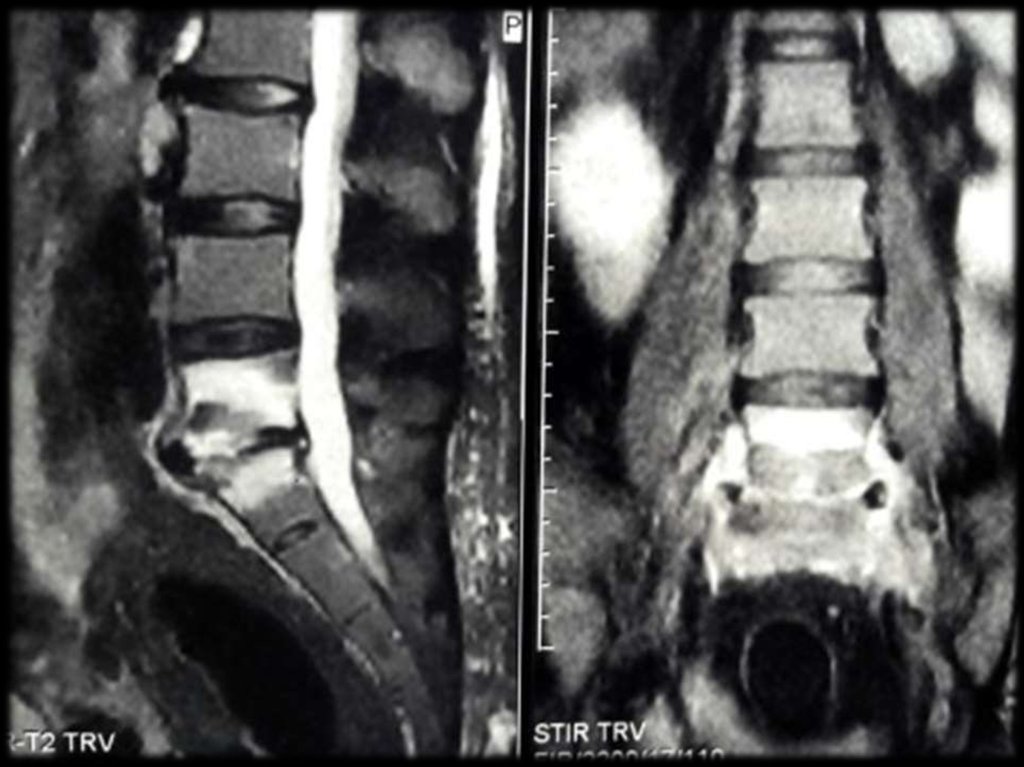

Слева — бруцеллезный спондилит поясничного

отдела позвоночника. Справа — двухсторонний

бруцеллезный сакроилеит.

Поражение позвоночника при хроническом бруцеллёзе